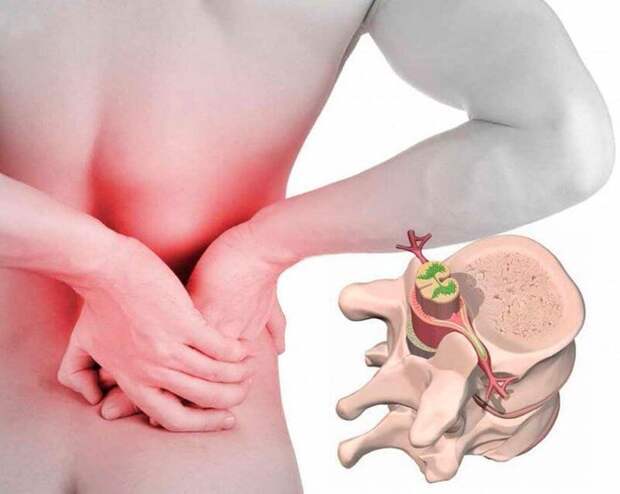

Остеохондроз пояснично-крестцового отдела позвоночника встречается наиболее часто. Дегенеративный процесс наблюдается обычно в нижнепоясничных дисках.

Основными синдромами заболевания являются следующие: люмбаго (поясничный прострел); люмбалгия – хроническая боль в пояснице; люмбоишиалгия проявляется болями в пояснице, распространяющимися на одну или обе ноги.